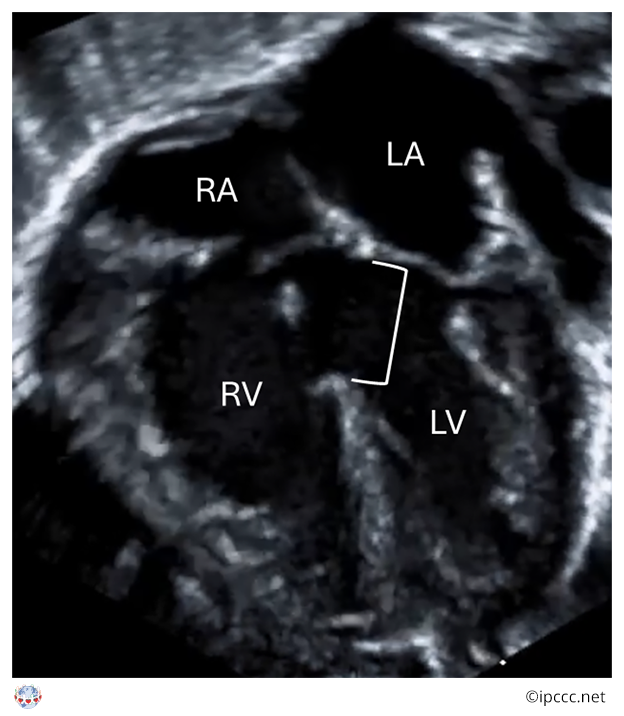

A congenital cardiac malformation in which there is a ventricular septal defect that usually, but not always, extends beneath the full annular length of the septal leaflet of the tricuspid valve and to the membranous septum, into the inlet component of the right ventricle in the absence of atrioventricular septal malalignment and of a common atrioventricular junction.

Echocardiogram